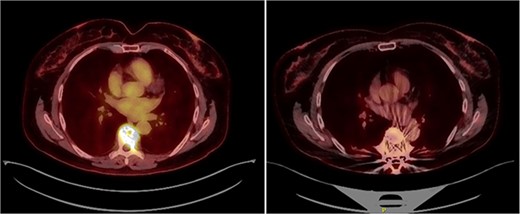

A second PET was performed and the case was derived to multidisciplinary meeting. Systemic disease was ruled out and diagnosis was established as intracompartmental Grade 1 chondrosarcoma colliding with intraosseous, extranodal DLBCL (Ann Arbor stage IE). In line with the R0 resection, chondrosarcoma was considered to be cured. In regards to DLBCL, immunochemotherapy with RCHOP (rituximab, cyclophosphamide, doxorubicin, vincristine, and prednisolone) was indicated by an oncological hematologist. By the end of the fourth cycle, PET showed no evidence of malignant disease, which indicated a complete metabolic response and therefore chemotherapy was discontinued (Fig. 9).

(left) PET scan prior to surgery showing pathological fracture at T7 with increased metabolical uptake (SUVmax 9.48). (right) PET scan by the end of fourth RCHOP cycle. No evidence of malignant disease. Slight metabolical uptake adjacent to spinal instrumentation (SUVmax 3.6) indicative of postsurgical changes.